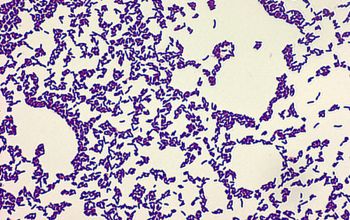

Gram positive irregular (short) rods,

lying single, in groups, or in irregular V-shape.

In older cultures the rods are shorter.